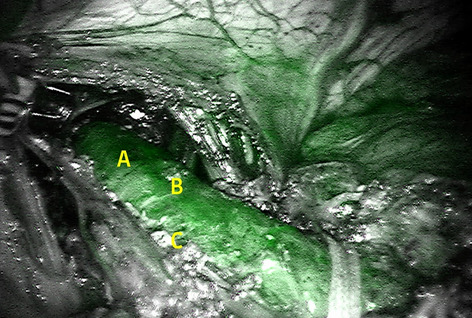

Methods: Analysis of our prospectively collected, IRB approved database of hybrid, open, and robotic esophagectomies was performed. Starting 01/2019, we implemented an updated robotic standardized anastomotic technique using a circular stapler and ICG (indocyanine green) for our RAMIE cases at our academic center (Picture 1). Outcomes of patients undergoing this standardized robotic Ivor Lewis esophagectomy for esophageal cancer from 01/2019 – 11/2020 were compared to our overall cohort from 06/2016–06/2020 (Hybrid/Open group).Propensity score matching comparing robotic to hybrid procedures will be performed and data will be presented upon the meeting.

Results: A total of 615 patients were analyzed. A total of 96 patients underwent a robotic assisted Ivor Lewis esophagectomy. Of these, a total of 56 patients underwent a robotic thoracic reconstruction using the updated standardized circular stapled anastomosis. A total of 64 patients were operated using an open approach and 455 underwent a hybrid procedure with a circular stapled anastomosis (Hybrid/Open group). Demographic and oncological data is shown in Table 1. Mean age was 63 years (range 46–80) in the robotic group and 63 years (range 33–91) in the hybrid/open group. Further details about postoperative complications are depicted in Table 2. One patient developed an anastomotic leak in the robotic group, resulting in an anastomotic leak rate of 1.8%. In comparison 63 patients (12%) developed an anastomotic leak in the Hybrid/Open group (p = 0.0132). Median length of stay (LOS) was 13 days in the robotic group (range 7–52), compared to a median LOS of 15 days (range 9–99) in the open/hybrid group.

Conclusion: A standardized circular stapled anastomosis in RAMIE cases for esophageal cancer may result in very low anastomotic leak rates and thereby positively influence outcomes in selected esophageal cancer patients.